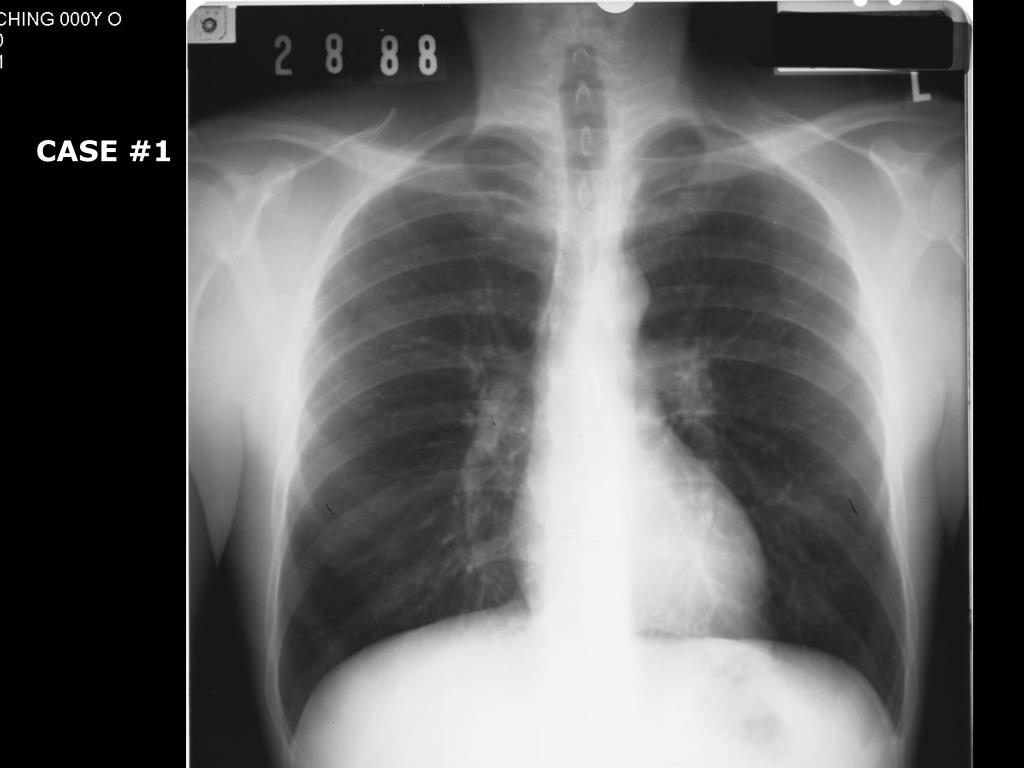

31. CASE #1

32. CASE #1 – Two weeks later Acute Shortness of Breath